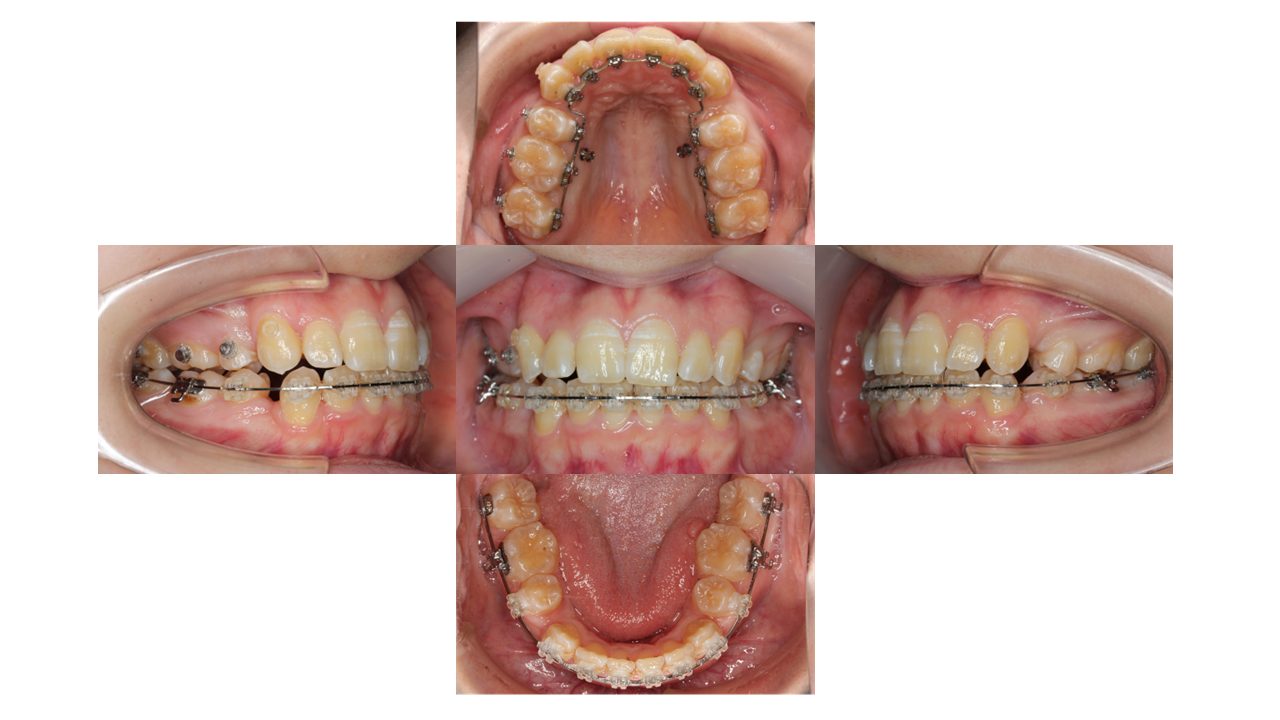

7カ月経過の口腔内の状態です。

全体の凸凹が改善しました。

上顎に歯科用アンカースクリューを埋入し、ゴムの力で前歯を引っぱりながら残りのスペースを閉じていきます。